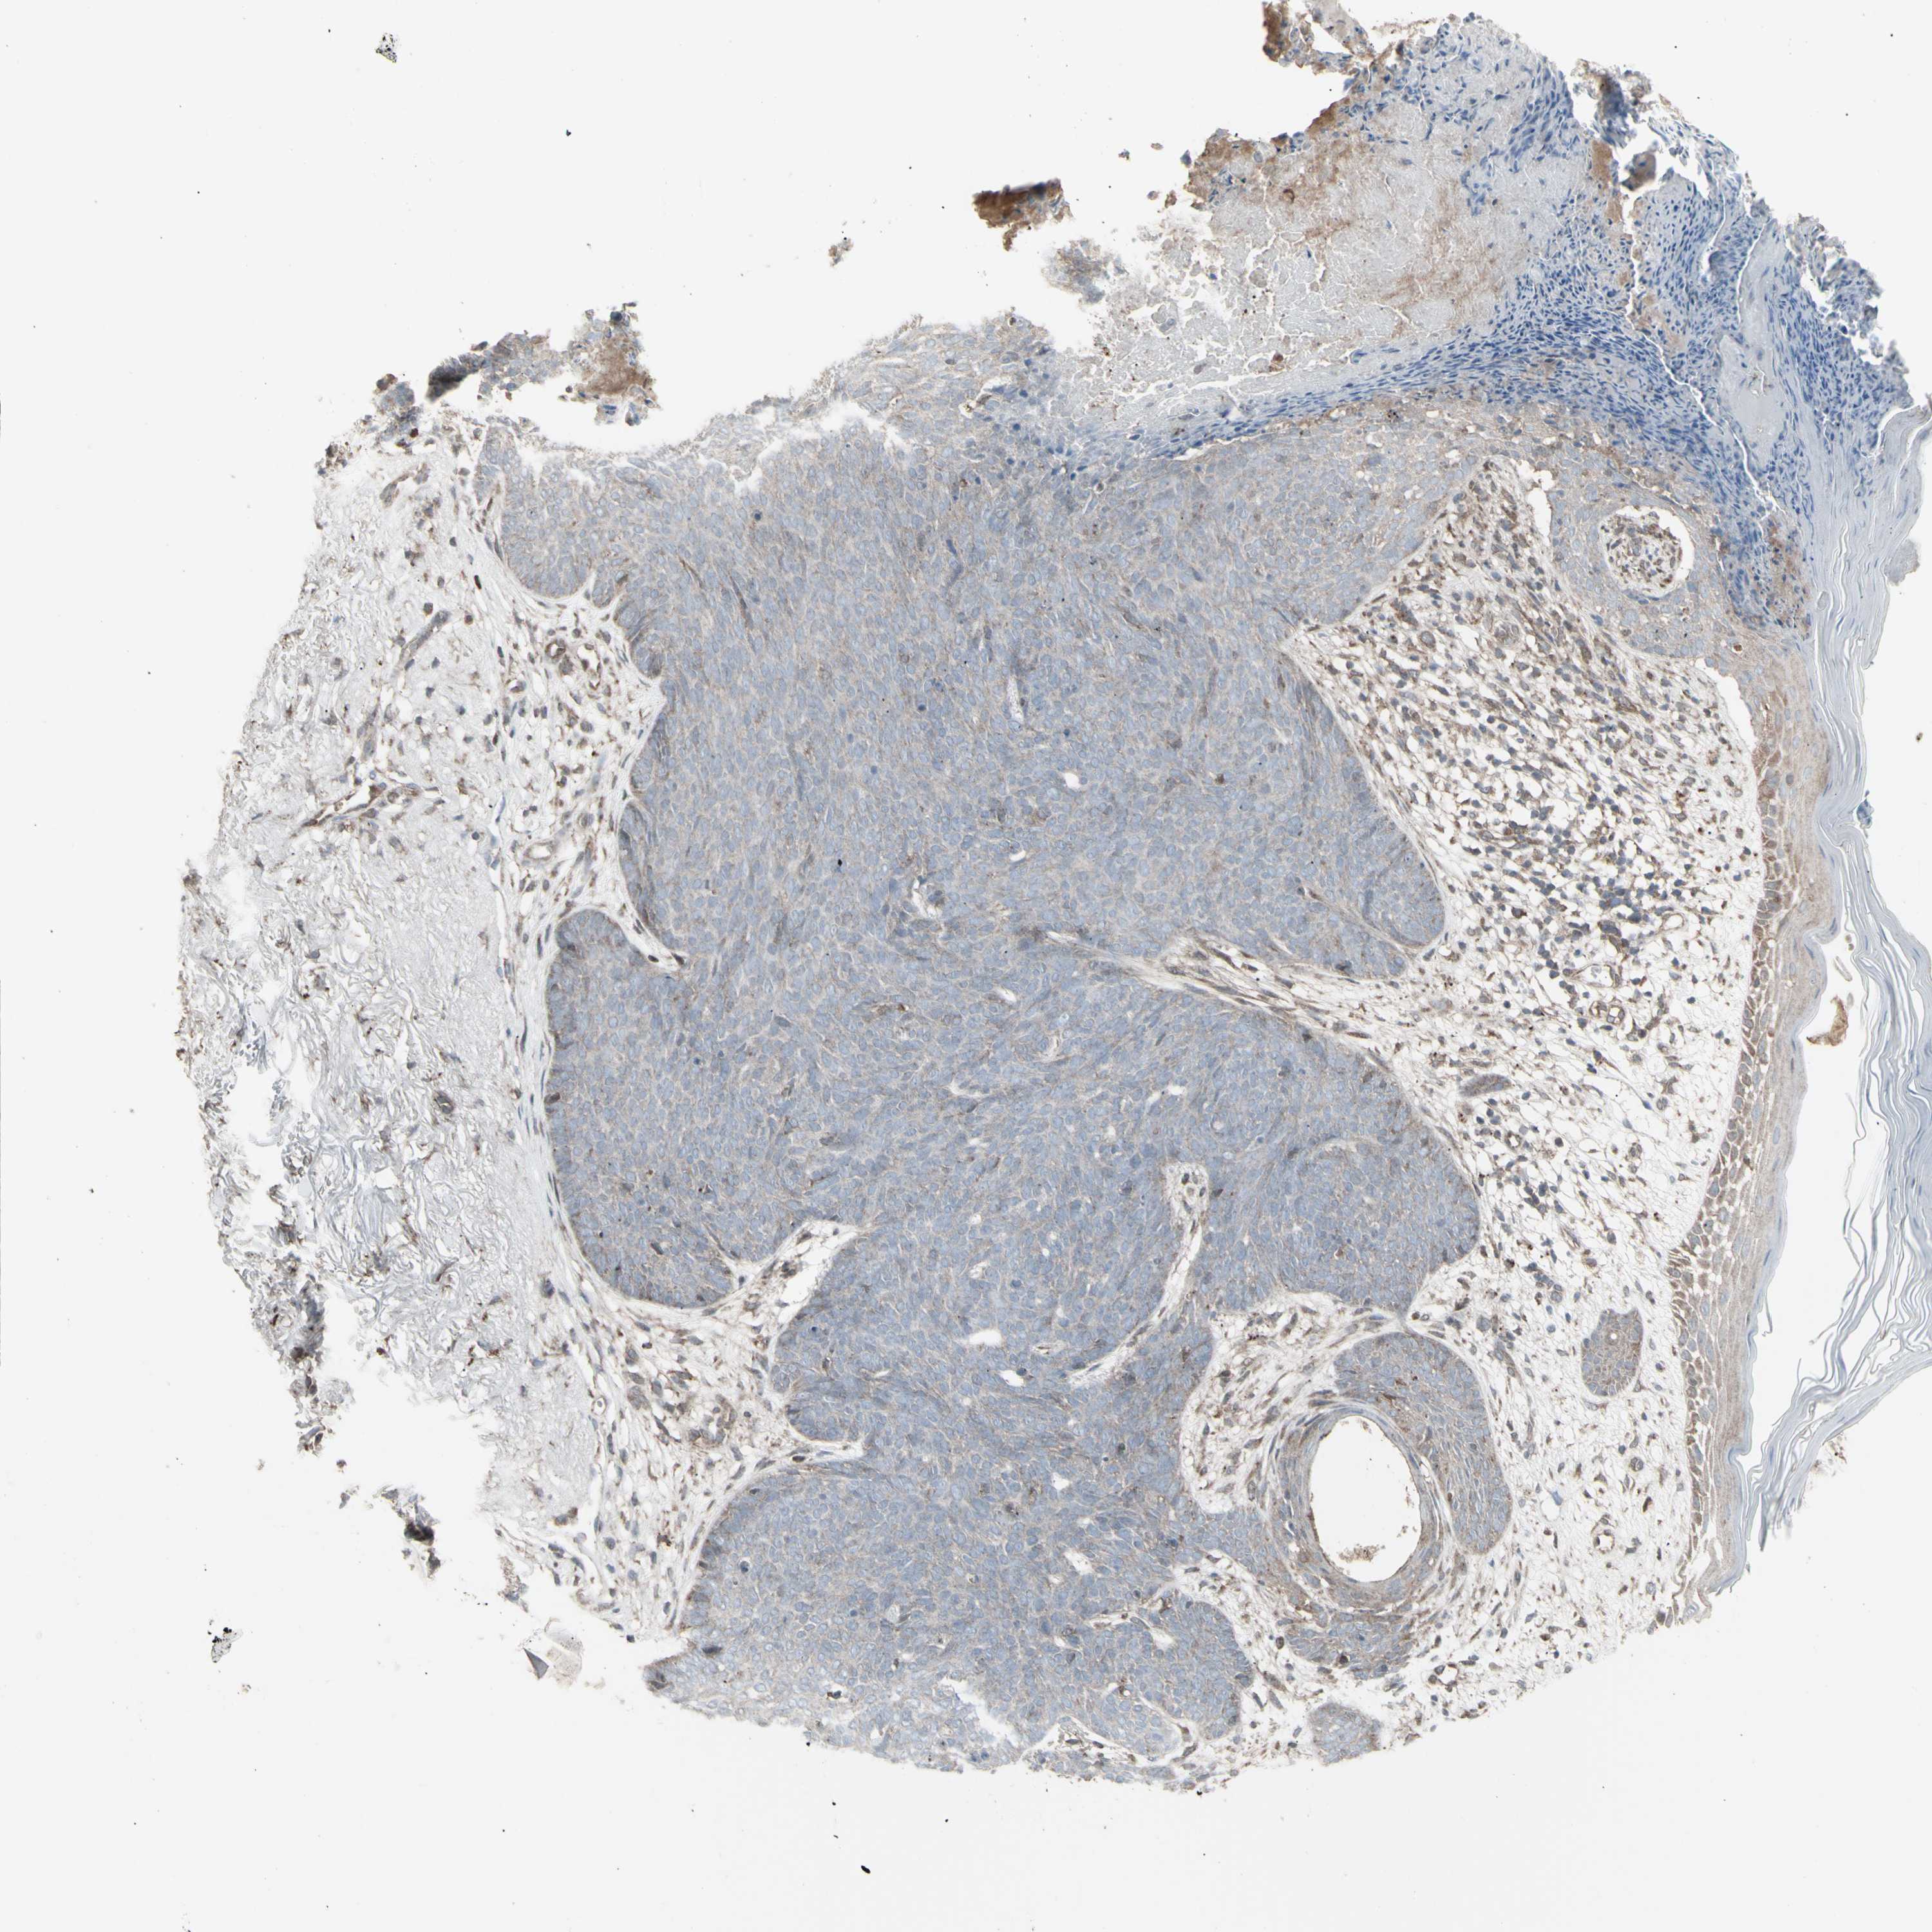

CANCER SKIN CANCER Show tissue menu

Basal cell and squamous cell cancer

SKIN CANCER - Protein expressioni

A mouse-over function shows sample information and annotation data. Click on an image to view it in a full screen mode. Samples can be filtered based on level of antibody staining by selecting one or several of the following categories: high, medium, low and not detected. The assay and annotation is described here.

Each image is clickable and will lead to virtual microscopy that enables deeper exploration of all samples and also displays staining intensity scores, fraction scores and subcellular localization as well as patient and tissue information for each sample.

Antibody HPA046758

Squamous cell carcinoma, NOS

Basal cell carcinoma